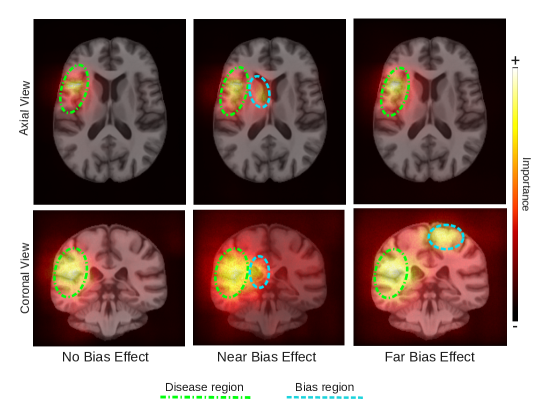

Saliency maps highlighted both the disease and the corresponding bias region in each of the bias scenarios (Figure 1). Quantitatively, weighted saliency scores demonstrated a higher intensity saliency within the regions affected by the bias effect for both the Near and Far Bias scenarios relative to the No Bias baseline (Figure 3).

Figure 1: Average SmoothGrad saliency maps of correctly classified “subjects” for the bias group in the disease class, for each bias scenario in the naïve models.